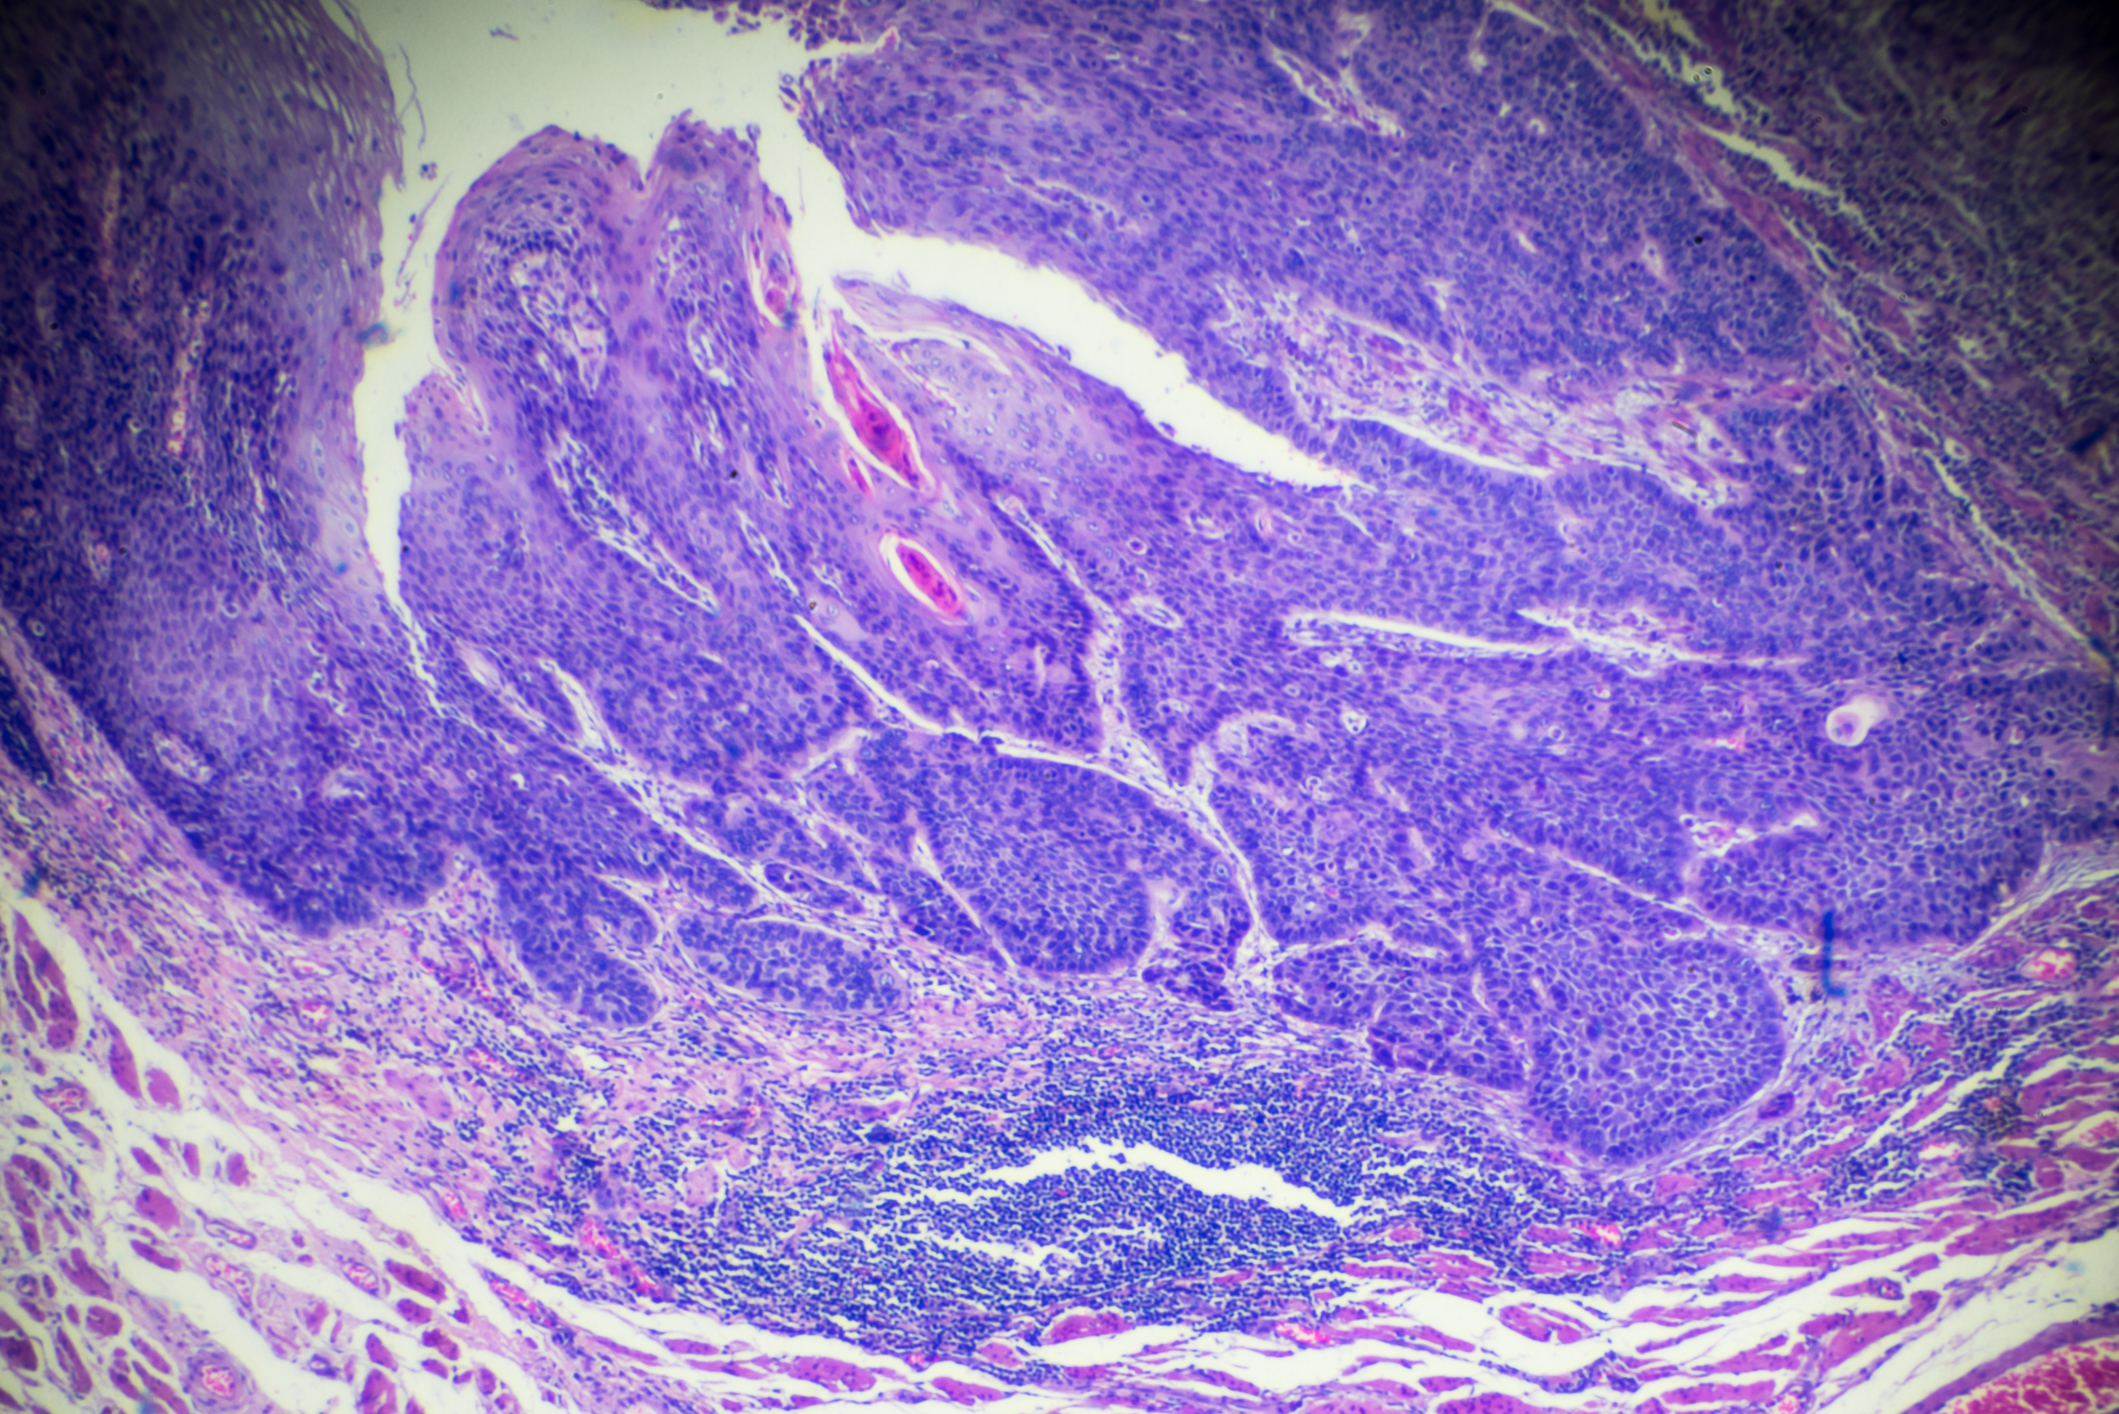

One of the main types of oesophageal cancer is squamous cell carcinoma, which begins in the squamous (skin-like) cells lining the middle and upper part of the oesophagus. Around half of all oesophageal cancers are of this kind.

The other most common type is adenocarcinoma, which first develops in glandular tissue in the lower part of the oesophagus. This occurs because the cells lining the oesophagus near the opening of the stomach have been overexposed to constant stomach acids. In most cases this is due to ‘reflux’, caused when the sphincter muscle at the end of the oesophagus lets digestive acids bubble up into the oesophagus.

Barrett’s oesophagus is a condition in which the normal flat-celled (squamous) lining of the oesophagus changes, becoming similar to the glandular tissue that lines the intestine. This change is called metaplasia, and it can progress to a more dangerous, pre-cancerous form called dysplasia. In a small number of patients, these changes can go on to form oesophageal cancer.